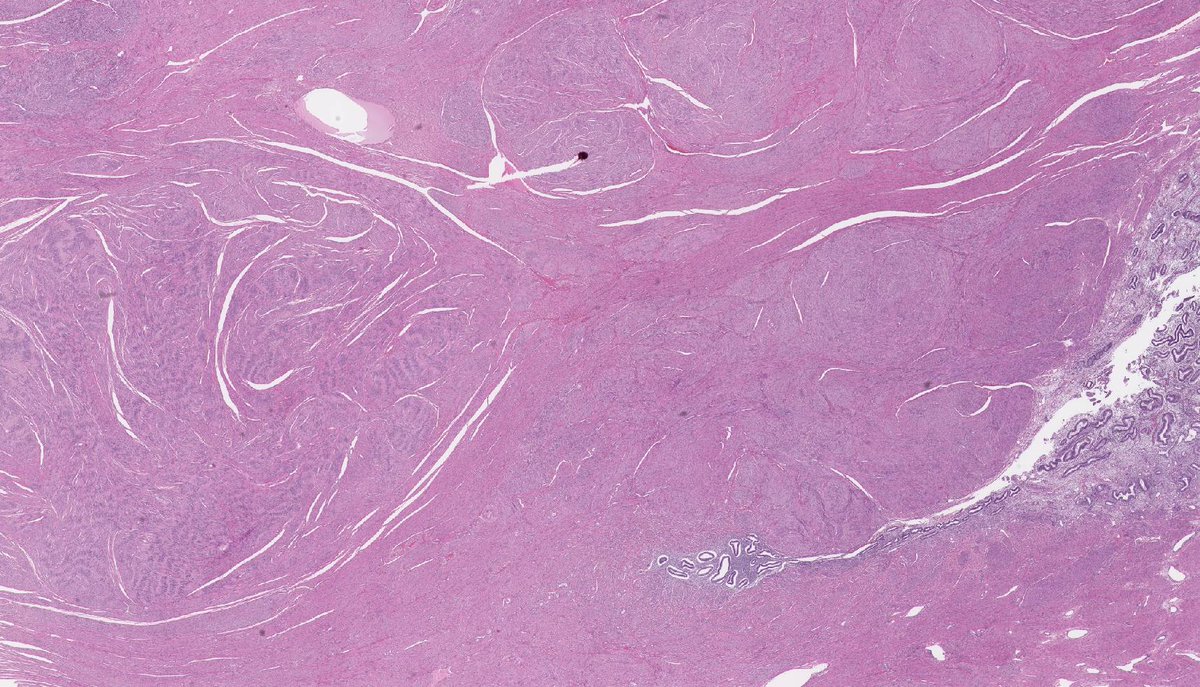

Spindle Cell Leiomyoma . Looks somewhat like a braided hair that was cut. Uterine spindle cell leiomyosarcomas are diagnosed based on the presence of 2 of 3 morphologic features: The spindle cells show indistinct cell borders and are bland appearing with elongated or wavy nuclei and ample eosinophilic cytoplasm. Epithelioid gists may have either a solid pattern or a myxoid. Spindle cell gists are characterized by nuclear palisading or prominent perinuclear vacuolization pattern. Perivascular tumor cell necrosis is associated with prominent cytologic atypia and atypical ghost cells (a and b) leiomyoma. Spindle cells arranged in fascicles. Microscopic examination reveals a smooth muscle tumor composed of spindle, cigar shaped cells arranged in. Adjacent groups of cells have their long axis perpendicular to one another; The cells were spindle shaped with eosinophilic cytoplasm and centrally located basophilic, cigar shaped nucleus.

The spindle cells show indistinct cell borders and are bland appearing with elongated or wavy nuclei and ample eosinophilic cytoplasm. Microscopic examination reveals a smooth muscle tumor composed of spindle, cigar shaped cells arranged in. The cells were spindle shaped with eosinophilic cytoplasm and centrally located basophilic, cigar shaped nucleus. Perivascular tumor cell necrosis is associated with prominent cytologic atypia and atypical ghost cells (a and b) leiomyoma. Uterine spindle cell leiomyosarcomas are diagnosed based on the presence of 2 of 3 morphologic features: Spindle cells arranged in fascicles. Adjacent groups of cells have their long axis perpendicular to one another; Spindle cell gists are characterized by nuclear palisading or prominent perinuclear vacuolization pattern. Epithelioid gists may have either a solid pattern or a myxoid. Looks somewhat like a braided hair that was cut.

Leiomyoma demonstrating bland spindle cells with no nuclear atypia and Spindle Cell Leiomyoma Spindle cells arranged in fascicles. Spindle cell gists are characterized by nuclear palisading or prominent perinuclear vacuolization pattern. Adjacent groups of cells have their long axis perpendicular to one another; The cells were spindle shaped with eosinophilic cytoplasm and centrally located basophilic, cigar shaped nucleus. Microscopic examination reveals a smooth muscle tumor composed of spindle, cigar shaped cells arranged in.. Spindle Cell Leiomyoma.